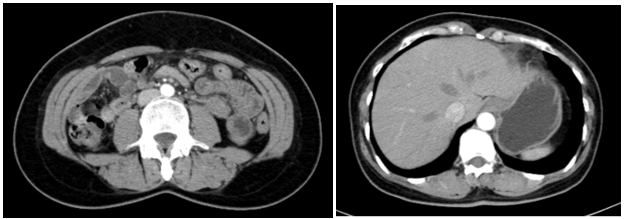

Cắt lớp vi tính lồng ngực:

Hình 2: Hình ảnh cắt lớp vi tính lồng ngực chưa phát hiện bất thường

Cắt lớp vi tính ổ bụng:

Hình 3: Hình ảnh cắt lớp vi tính ổ bụng chưa phát hiện bất thường